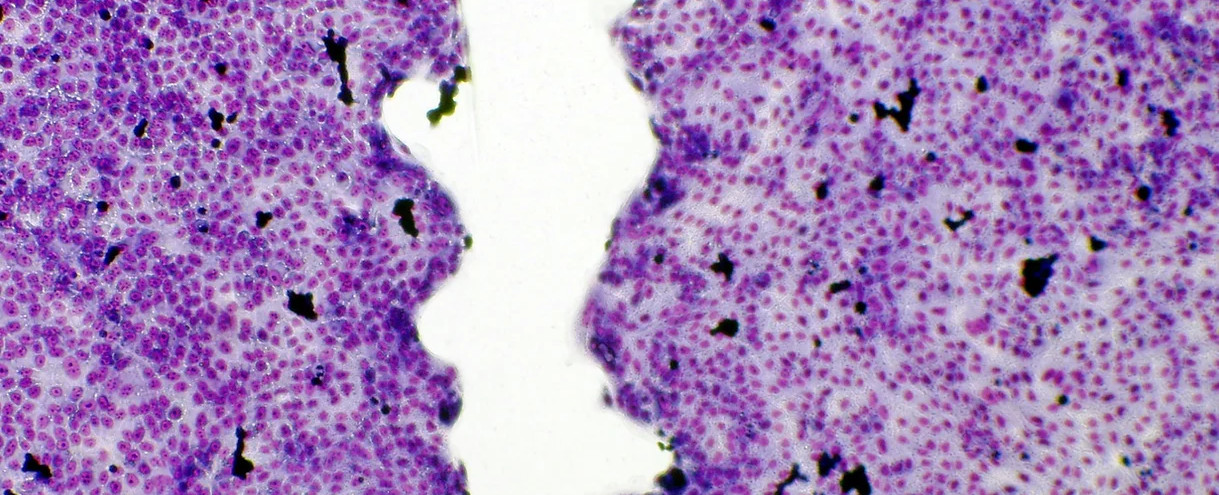

Example of cell regeneration

Compared to the untreated control group (image above) the identically created connective tissue cells in the image below increased in size by more than 55% grows together faster resp, regenerated. A ZenPad was placed under these connective tissue cells.